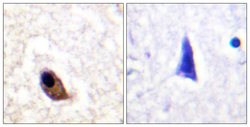

STJ91307 IHC

Full details

Method: